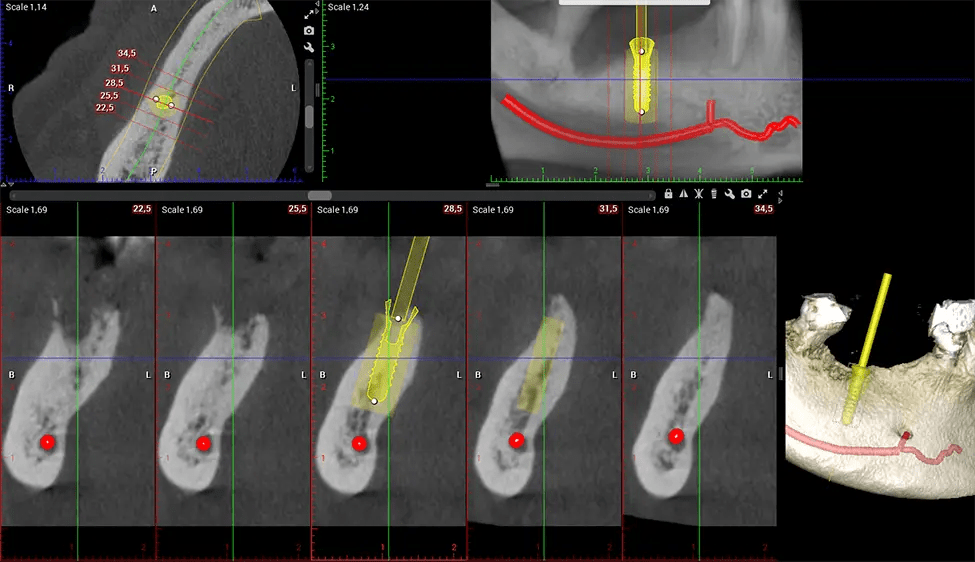

When paired with extractions, dental implant placement, or bone grafting, CBCT technology can provide you with a quicker and much more comfortable experience. This is because the 3D image provides a more detailed picture of your entire oral cavity, allowing your dentist to walk you through each step of the process before it occurs. This often helps patients feel more prepared and comfortable overall, especially if they have had a traumatic experience with past dental treatments.

After the scanning process, the captured X-ray images are processed by the CBCT software, which applies algorithms to reconstruct a detailed 3D image of the scanned area. The software compiles these individual X-ray images and creates a digital 3D representation of the patient’s anatomy. The reconstructed 3D CBCT image can be viewed and analyzed by the dentist or radiologist. This image can be manipulated, rotated, and zoomed in or out to examine specific structures and evaluate the patient’s condition.

Planmeca Viso G7 CBCT ( Cone Beam CT Scan ) is designed to surpass the demands of industry leaders, specialists, and large institutions. It’s has a large ø25×30 cm sensor with four built-in cameras. It can capture unlimited volume sizes from a ø3×3 cm to a ø30x30cm volume capturing the skullcap through C7 on the cervical spine. The Planmeca Viso G7 offers the industry’s largest single volume scan of ø30×19 cm. It’s poised to handle advanced imaging modalities such as Planmeca ProFace® and Planmeca 4D™ Jaw Motion technology. The occipital head support allows an unimpeded view of facial tissue.